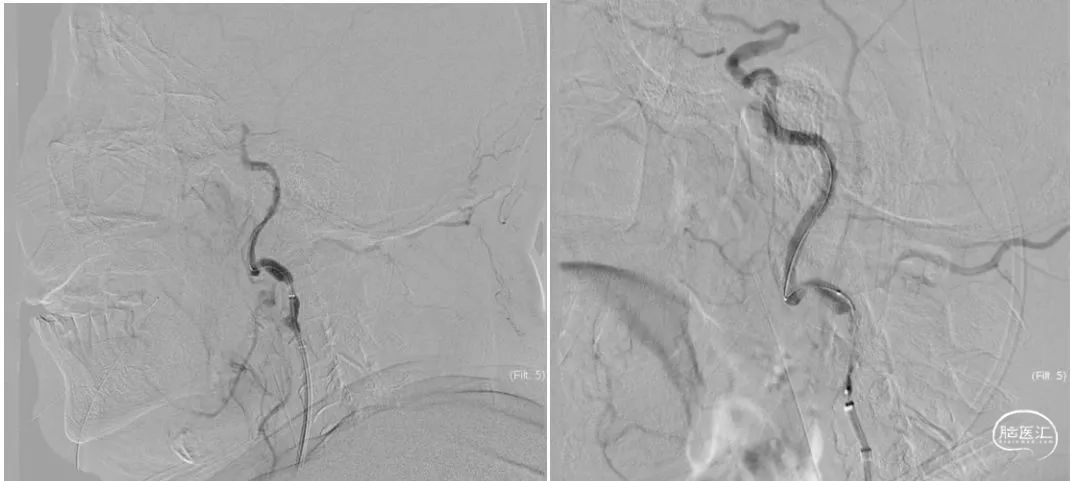

0.014微导丝通过颈动脉闭塞处,采用3.0*20mm心玮披荆颈动脉球囊扩张导管预扩张。

心玮通堑远端通路导管通过颈动脉起始病变处,反复抽吸后造影,大脑中动脉M1段闭塞,微导管及微导丝通过病变后撤出微导丝,通过微导管造影明确闭塞远端。

释放6*30mm心玮捕星颅内取栓支架,采用SWIM技术进行取栓,大脑中动脉再通良好,大脑前动脉A3段存在血栓逃逸(红色箭头),动脉团注替罗非班注射液10ml。

释放心玮灵笼栓塞保护器,采用5*30mm心玮披荆颈动脉球囊扩张导管再次进行扩张,随后释放6-8*40mm颈动脉支架,再次通过导引导管造影,血管再通良好。